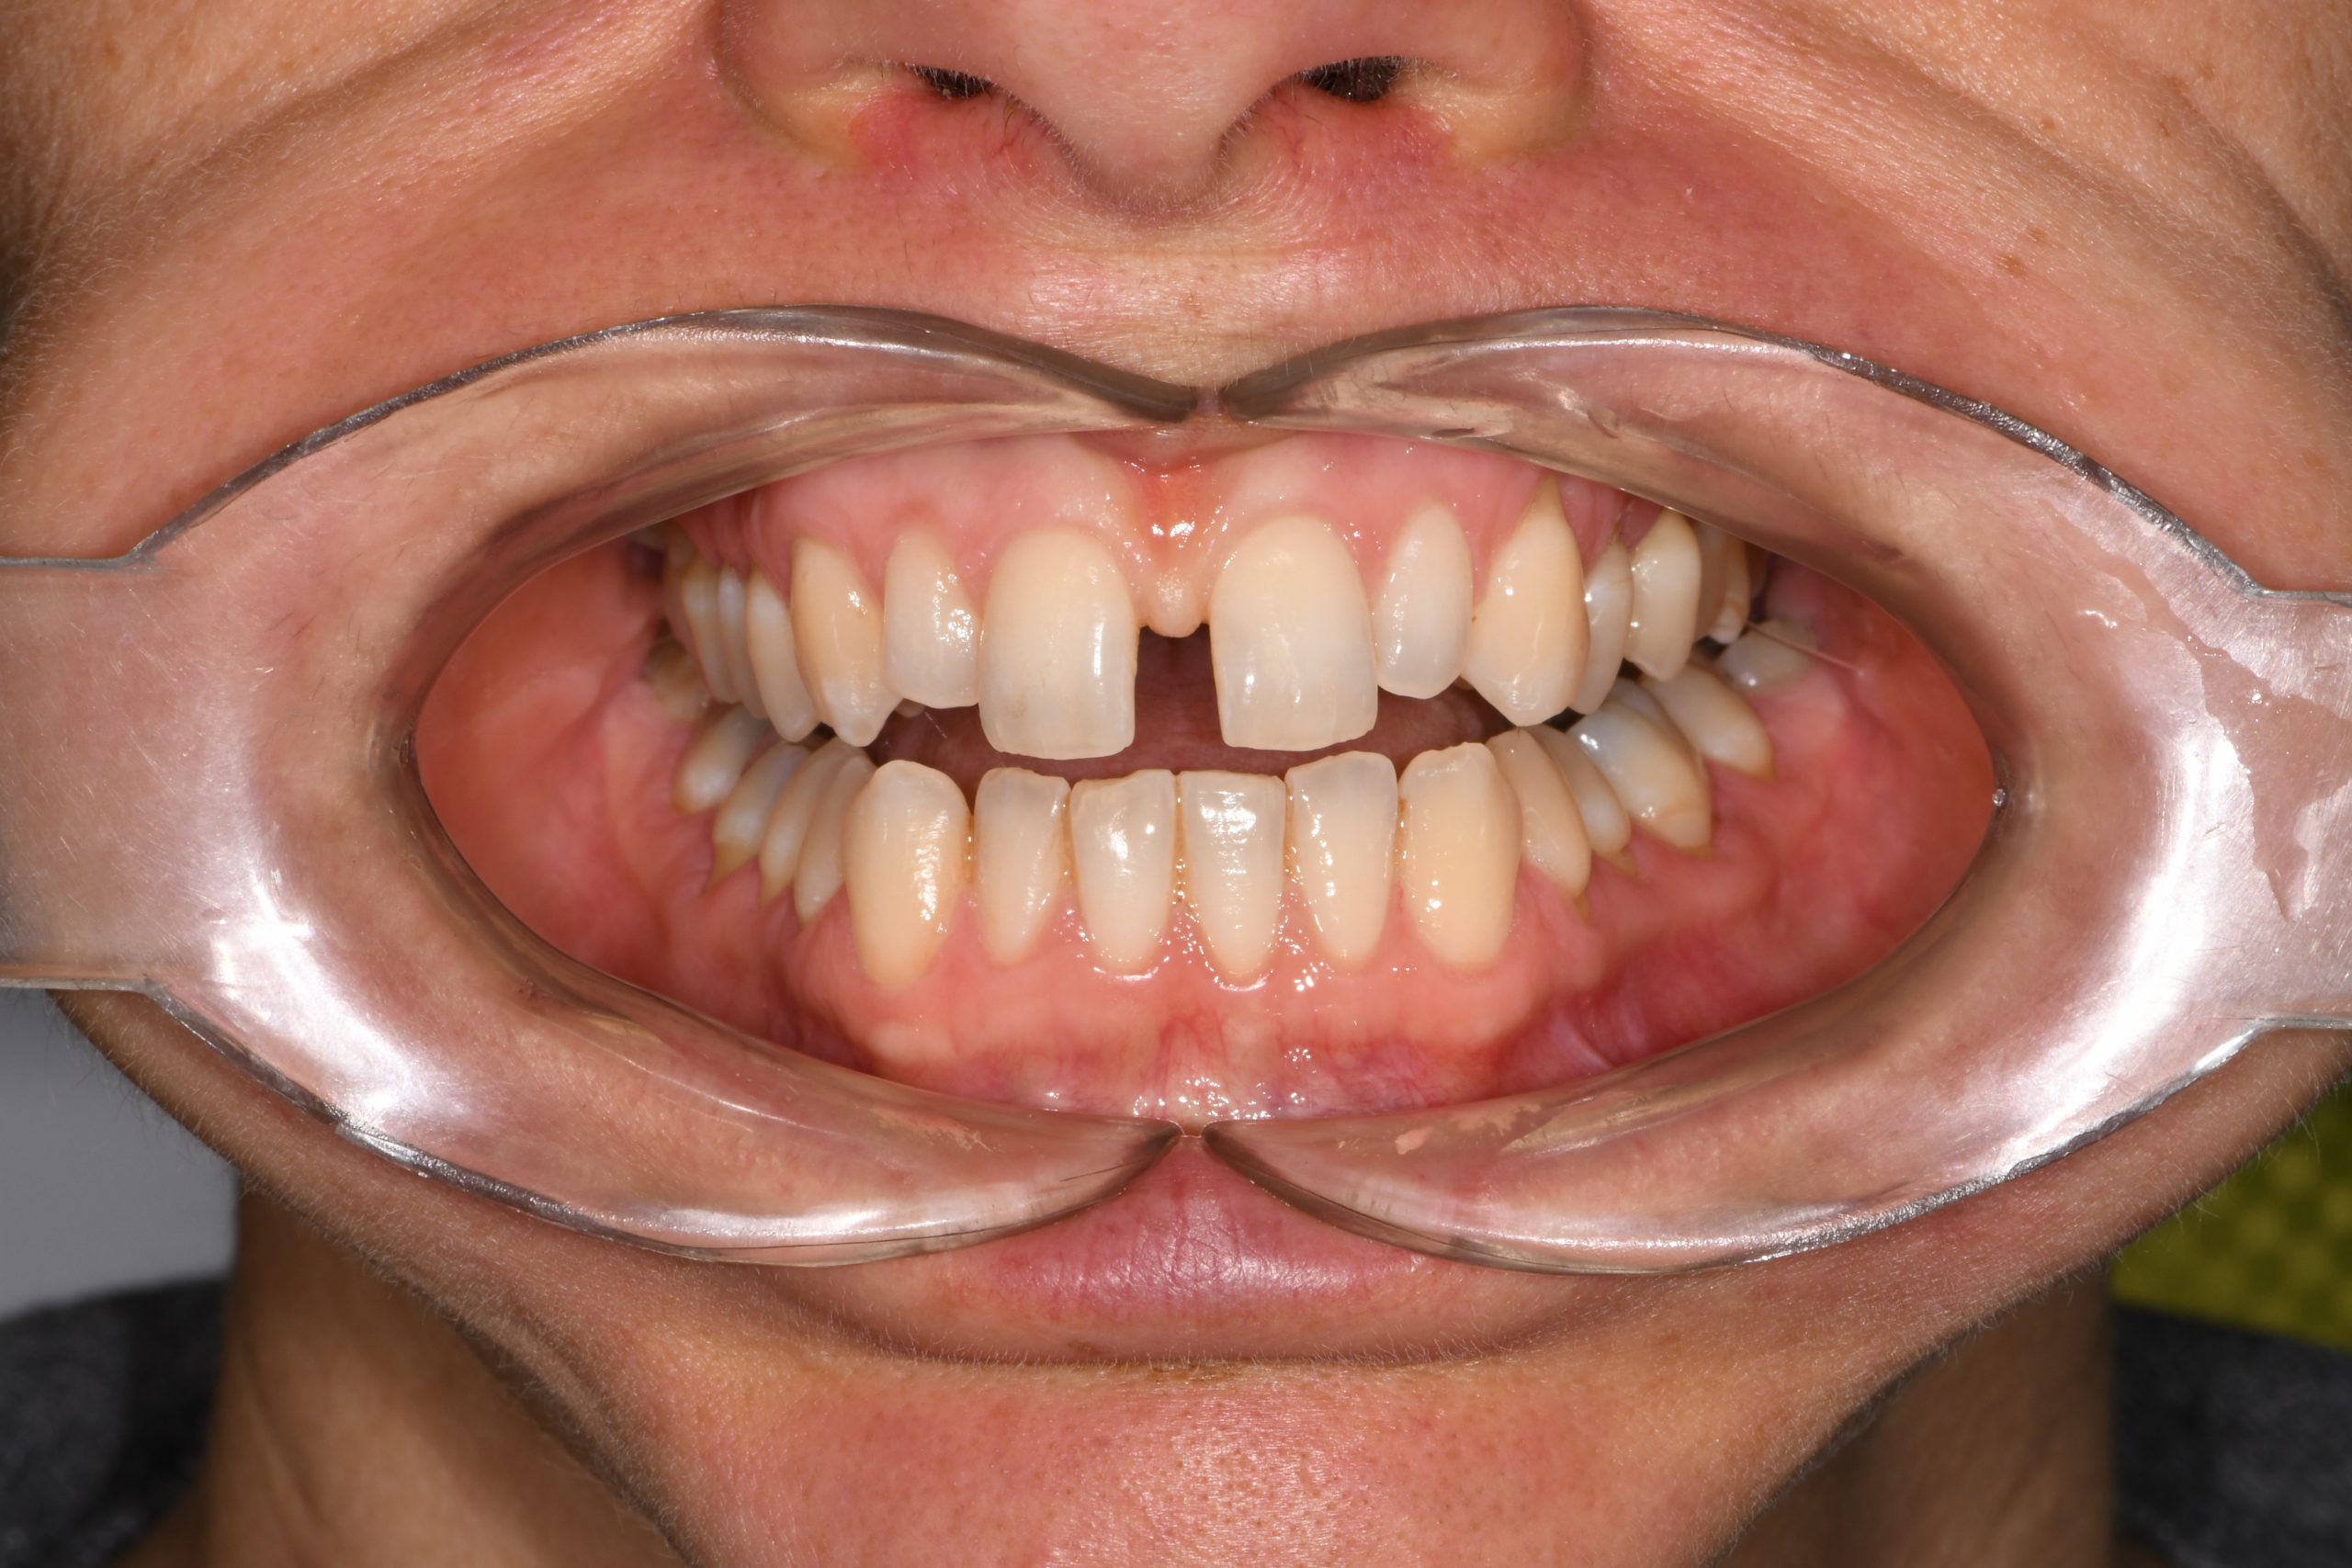

Az elmúlt évekből rengeteg szakmai referenciát tudnánk bemutatni, amelyek különböző fogszabályozási problémákat oldottak meg. Válogatva a több száz esetből, ezen az oldalon olyan képeket, információkat igyekeztünk bemutatni, amelyeknek a segítségével a jövőbeni pácienseinknek azt tudjuk üzenni: A Te fogsorod is lehet gyönyörű!

(Képeket a Pácienseink külön írásos beleegyezésével mutatjuk be!)